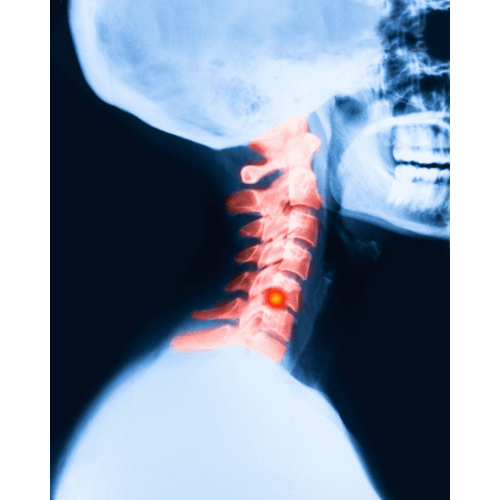

Diagnosing a C5-C6 herniated disc usually involves a combination of physical examinations, where doctors check for pain distribution and nerve function, and imaging tests like MRI or CT scans, which provide a detailed look at the spinal structures.

The cervical spine, a marvel of flexibility and support, consists of seven vertebrae, with the C5-C6 segment being particularly noteworthy.

This segment, located in the lower part of the neck, plays a pivotal role in supporting the head and enabling a wide range of motion.

The C5-C6 disc, sandwiched between the fifth and sixth cervical vertebrae, is responsible for cushioning these bones and facilitating movement.

When this disc herniates, it means the inner gel-like substance breaks through its tougher exterior, potentially causing nerve irritation or compression.